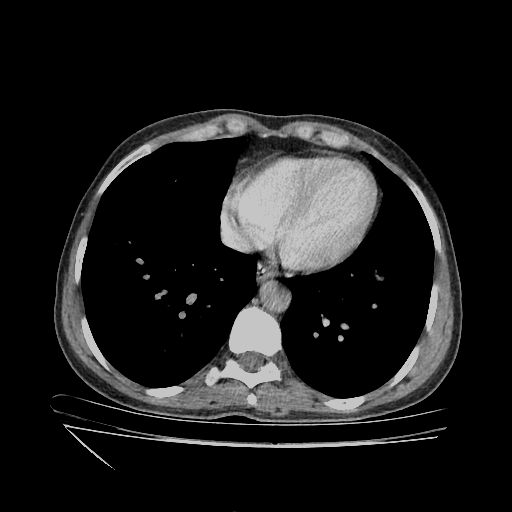

Targeted Slice 70 - Mediastinum Window Analysis (Generated vs Real Venous)

0.726

Mediastinum SSIM

59.9

Mediastinum RMSE

23.5

Mediastinum MAE

Average Mediastinum Window Metrics Across All Slices (112 slices) - Generated vs Real Venous

0.697

Mediastinum SSIM (Avg)

53.0

Mediastinum RMSE (Avg)

21.9

Mediastinum MAE (Avg)

Generated VENOUS CT scan (A→B translation)

No window - Raw intensity values

Mediastinum window (WL 40, WW 400 β†’ Low βˆ’160, High +240)